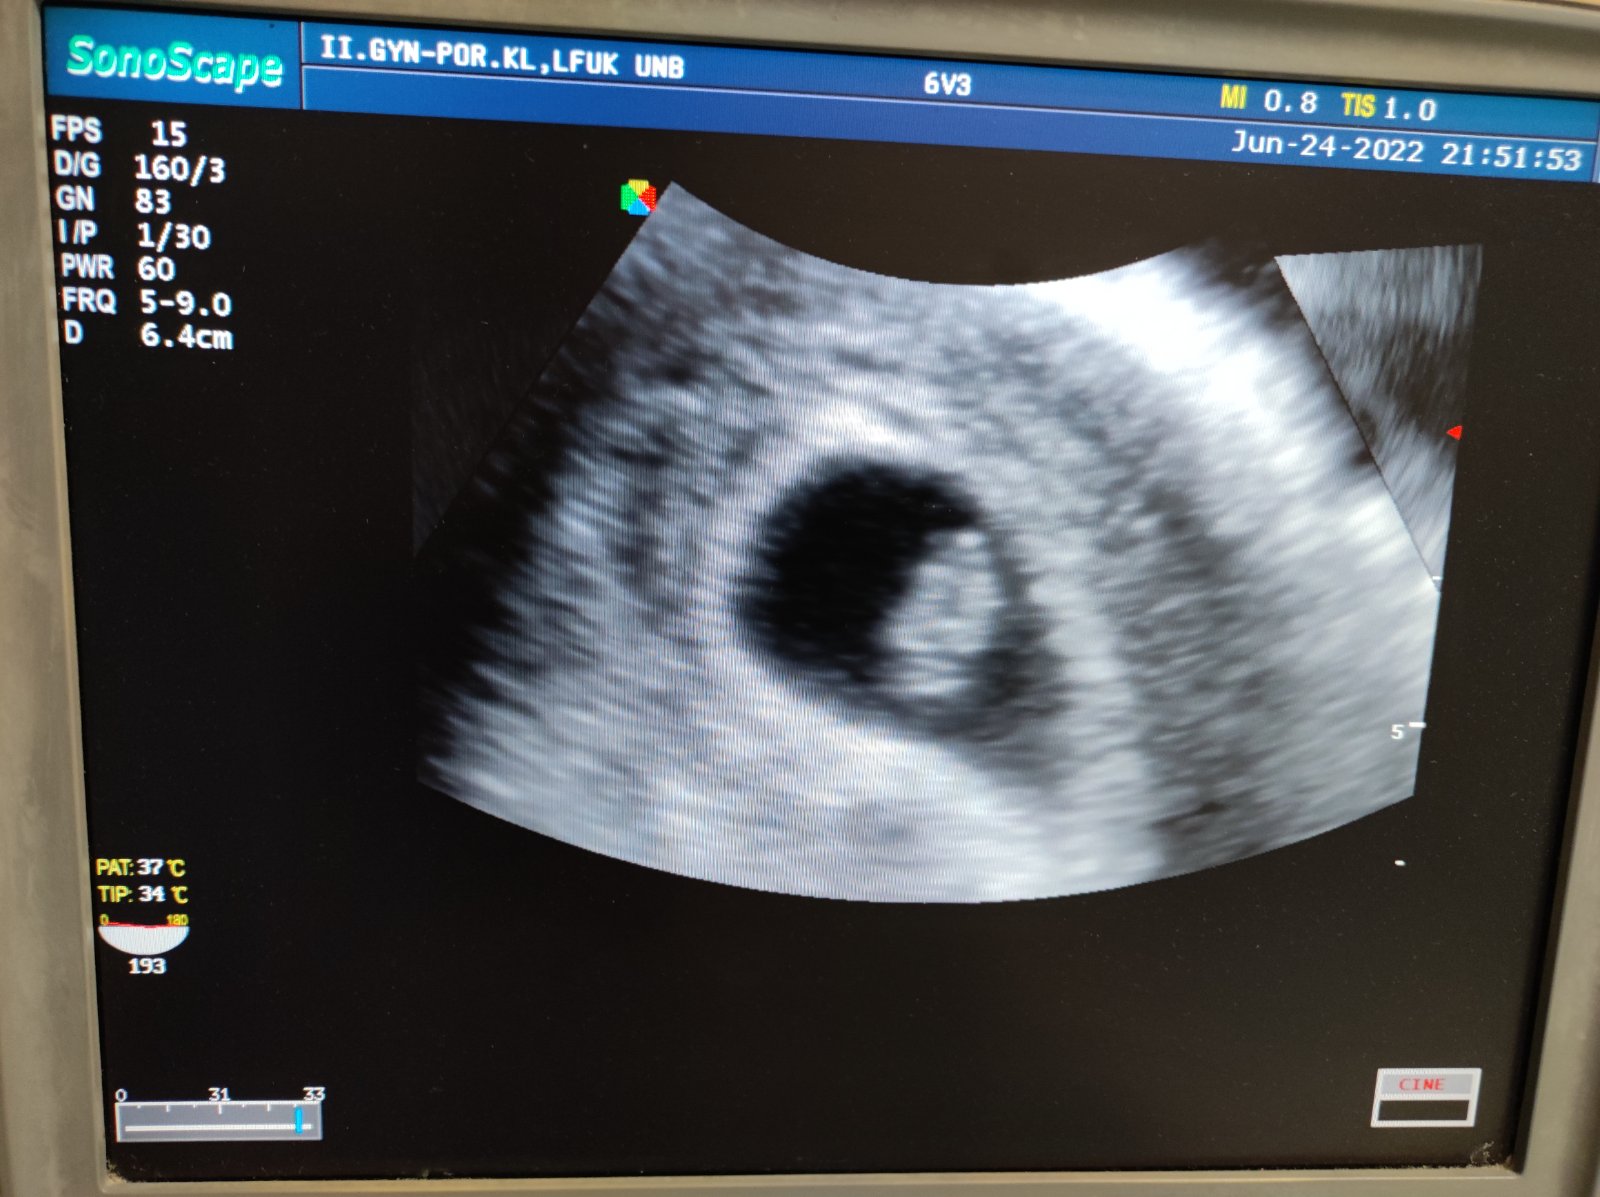

Vdaka bohu za tehotensku knizku 🙏🙏🙏

Sla som na wc a bum krv jasna cervena pri utreti. Tak som hned sla na pohotovost. Zlakla som sa a teda kedze mame ist to oznamit rodine chcela som vediet co sa deje. Nastastie ako tehotnu ma vysetrili okamzite.naozaj na prekvapenie som necakala ani minutu.lekar sice ma zdžubal ze som prisla hned pri nejakom slabuckom krvacani, ze mam vlozku cistu cistu,ze on by svoju zenu na pohotovost neposlal.ze keby vysetroval kazdu ktora zakrvaca tak by nerobil nic ine. No ale ja som nazoru ze radsej 100x zbytocne ako nieco zanedbat. Pri vysetreni videl kde to zakrvacalo niekde v krcku, ze vyzera byt vsetko ok. Dal mi pocut srdiecko, vyrastli sme o milimeter od stvrtku. Predpisal mi utrogestan.tak dufam,ze uz nebudem ani spinit ani nic...